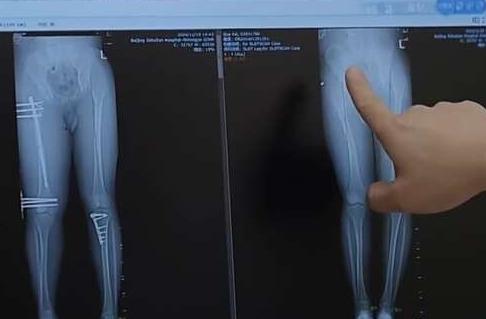

术后麻烦不断 禁而不止的“断骨增高” 有多坑?